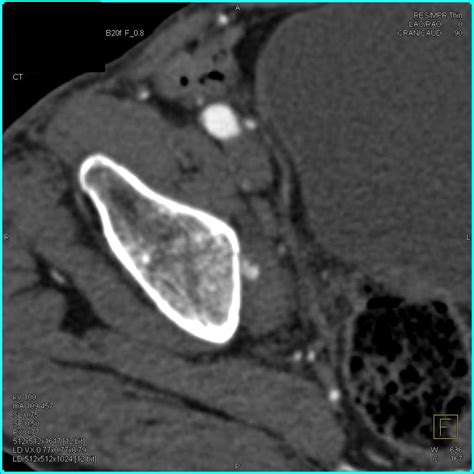

Diagnosing hip joint effusion typically involves a combination of physical examination, medical history, and diagnostic tests. The diagnostic process may include:

• Imaging Tests: X-rays, MRI, or ultrasound to visualize the hip joint and detect fluid accumulation.

• Joint Aspiration: Removing a sample of the fluid from the hip joint for laboratory analysis.

Joint aspiration is particularly useful for identifying the cause of the effusion, such as infection or crystal deposition diseases like gout.